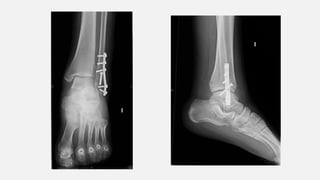

• 14/05/2019  intervingut. Abordatge lateral sobre el peroné. Neteja del focus de

fractura. Reducció i fixació amb pern i fixació amb placa 1/3 canya de 6 orificis.

RX TURMELL AP i LAT (16/07)